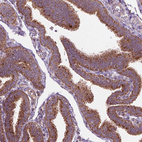

Immunohistochemical staining of human skin shows strong cytoplasmic granular positivity in squamous epithelial cells.